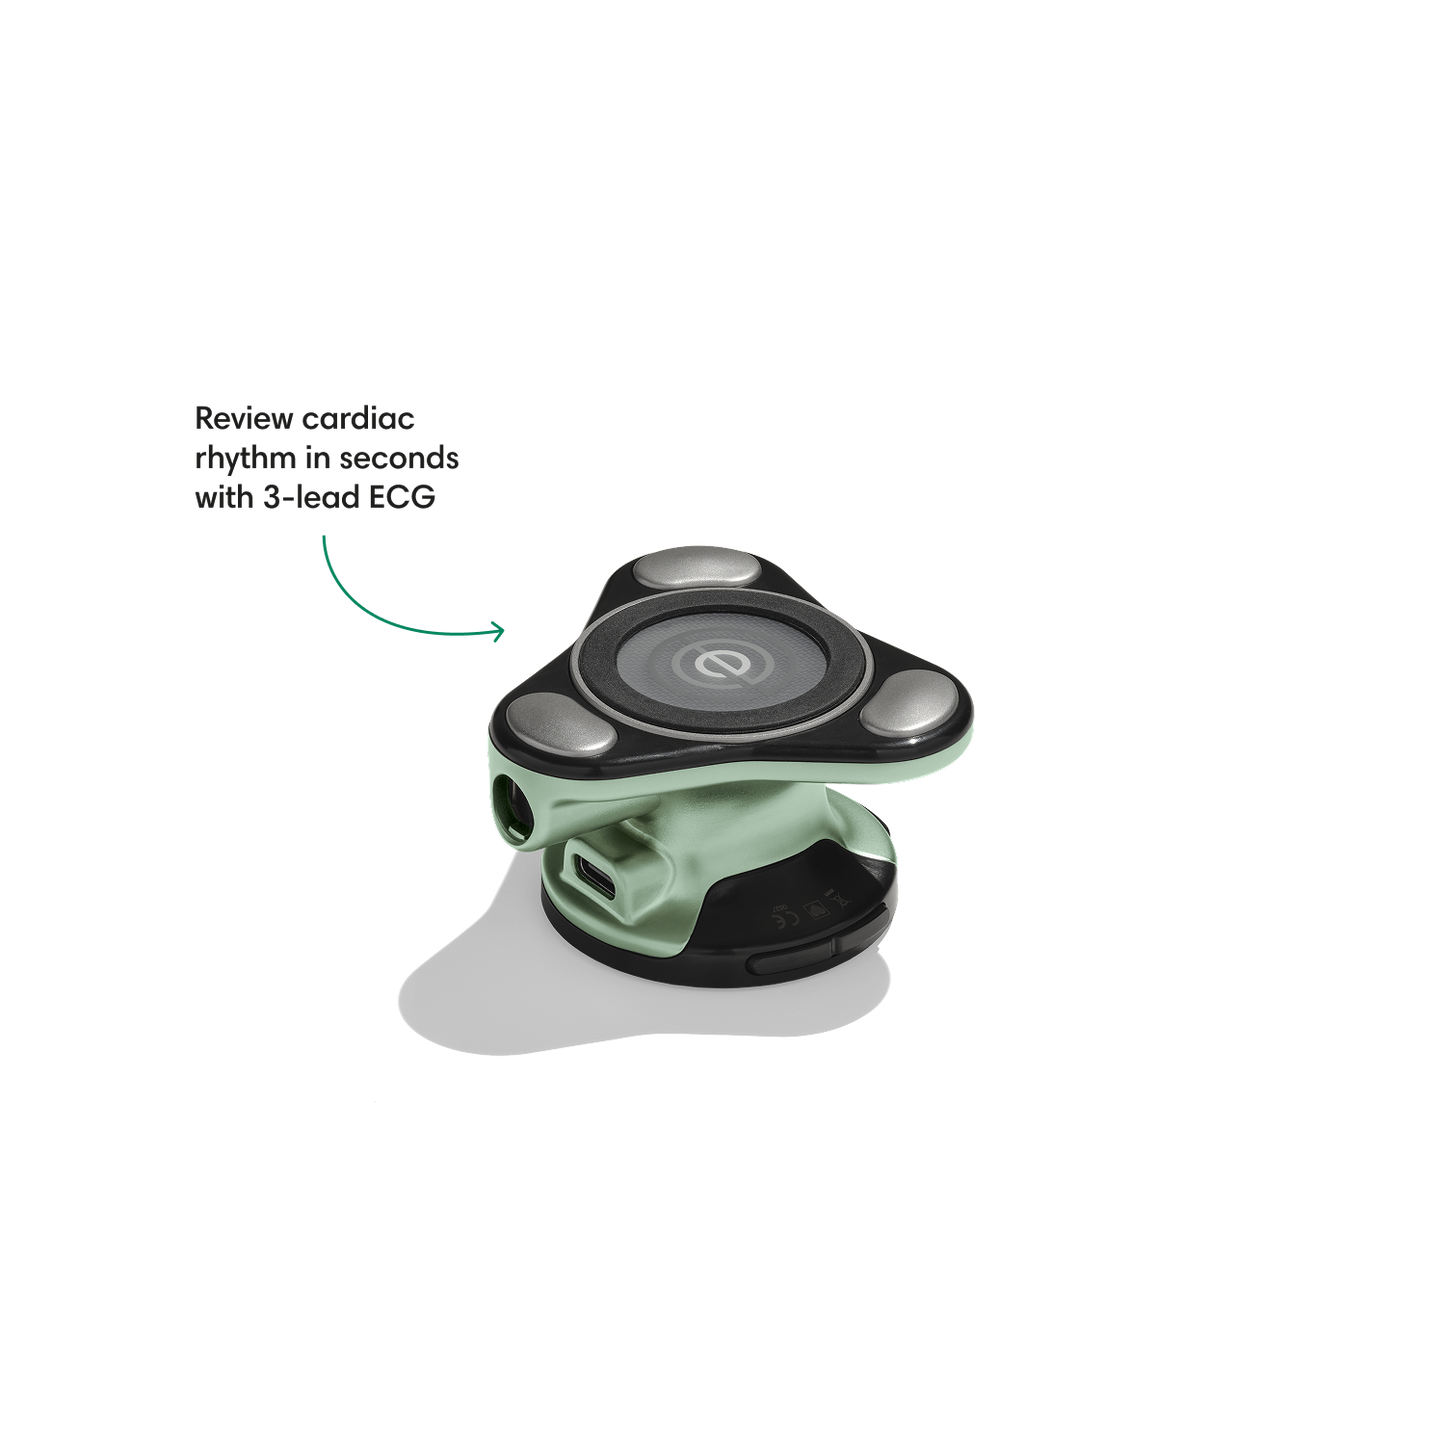

Go beyond sound alone.

For the first time ever, measure heart rate, visualize 3-lead ECG, and see detection results — right on a built-in, full-color display.